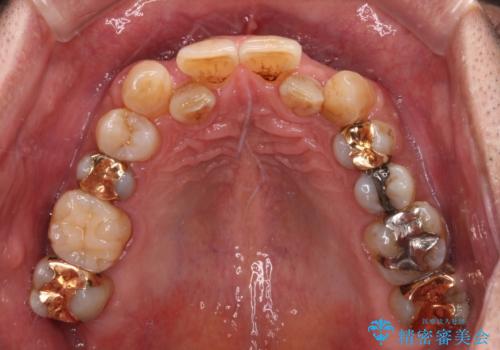

- 下顎両側の欠損と上顎前歯のデコボコを気にして来院された患者様です。

デコボコは今まで気にせずにいたそうですが、奥歯の欠損改善を機に、矯正治療に興味があるので、相談したいとのことでした。

奥歯に欠損が多く、矯正治療はやや難航することが予想されますが、患者様の希望もあり、上顎左右小臼歯を1本ずつ抜歯し、ワイヤー装置にて矯正治療を行うこととしました。

矯正歯科治療を行うに当たり、痛みや違和感を感じている歯の根管治療を行い、矯正治療中にインプラント埋入し、補綴治療と矯正治療を同時に終了できるように進めて行くこととしました。